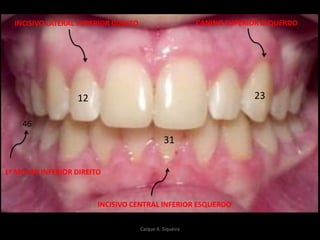

12

46

23

31

INCISIVO LATERAL SUPERIOR DIREITO

INCISIVO CENTRAL INFERIOR ESQUERDO

1º MOLAR INFERIOR DIREITO

CANINO SUPERIOR ESQUERDO